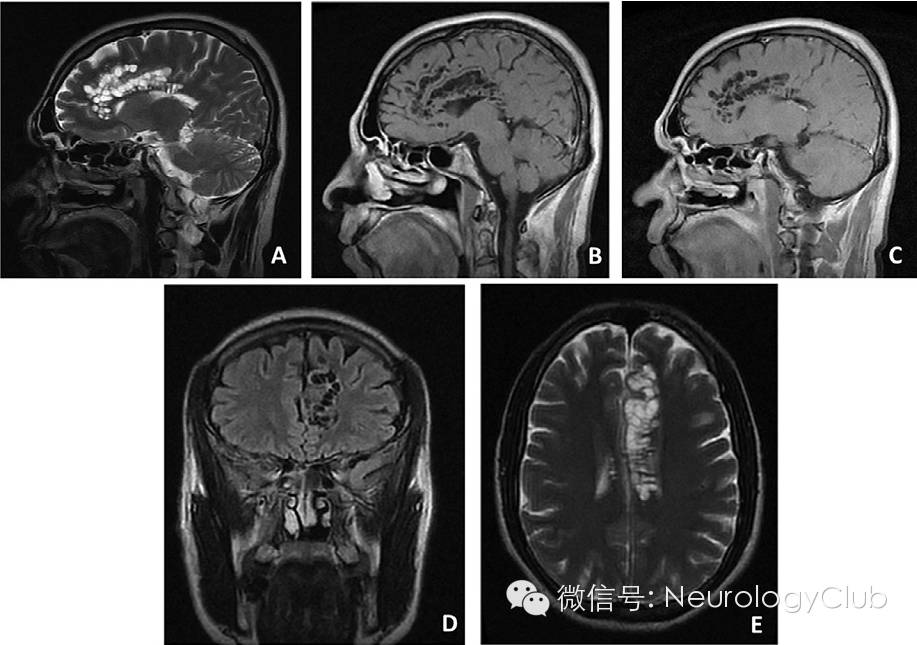

患者至当地医院行头颅MRI提示颅内多发囊性病灶,主要位于左侧额上回,扣带回及皮质下白质,胼胝体也有受累。灶周无水肿,无占位效应或中线移位。增强后病灶无强化。

(A:T2WI;B:T1WI;C:T1+C;D:T1WI;E:T2WI)